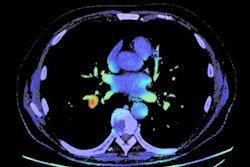

The OSIC Pulmonary Fibrosis Progression competition, which is administered by data science company Kaggle, will run through October 6. Participants will be tasked with creating machine-learning techniques to predict the severity of lung function decline in a patient with idiopathic pulmonary fibrosis based on a CT image and metadata, as well as baseline forced vital capacity.

"If successful, patients and their families would better understand their prognosis when they are first diagnosed with this incurable lung disease," the OSIC wrote. "Improved severity detection would also positively impact treatment trial design and accelerate the clinical development of novel treatments."